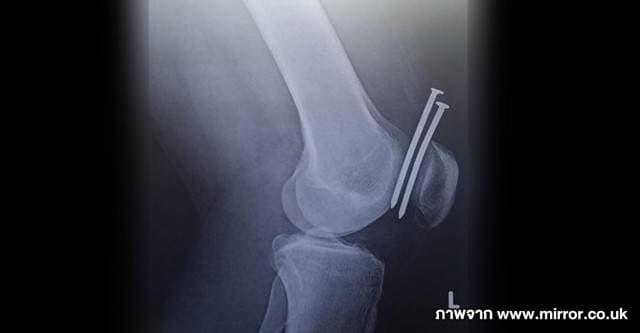

เผยภาพฟิล์มเอ็กซ์เรย์สุดช็อก ช่างไม้มือใหม่ชาวสหรัฐฯ พลาดยิงตะปูเสียบหัวเข่า